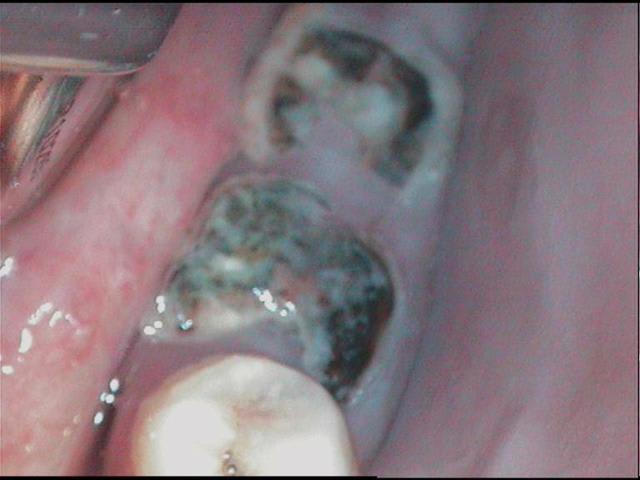

13 ans, je vous livre en vrac et dans n'importe quel sens

je m'en vais donc naviguer quelques temps entre pulpites et nécroses, calmer les pleurs, resorber les granulomes, ré équilibrer le "risque carieux"

j'ai passé les détails, aucune dent indemne de toute manière, tout est comme ça , les inc md itou

techniquement je dois etre loyal, les photos font reculer, j'ai reculé aussi en bouche, mais c'est plus impressionant au premier abord, dans le détail tout peut se jouer comme le montre cette radio

alors: les pulpites et granulomes en prems, ensuite les endos inévitables, ensuite des verre iono ou eugenates partout, ré équilibrer le risque et motiver, ensuite caler l'occlusion avec les 8 pm dans un premier temps(parceque là j'y pige rien) ensuite l'ortho (parceque là c'est pas présentable)enfin toutes ces sortes de chose quoi...